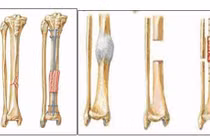

Lấy xương chậu ghép vào cánh tay điều trị khớp giả

Khớp giả là tình trạng xương không liền sau phẫu thuật. Điều trị khớp giả là một quá trình khó khăn, phức tạp và lâu dài.